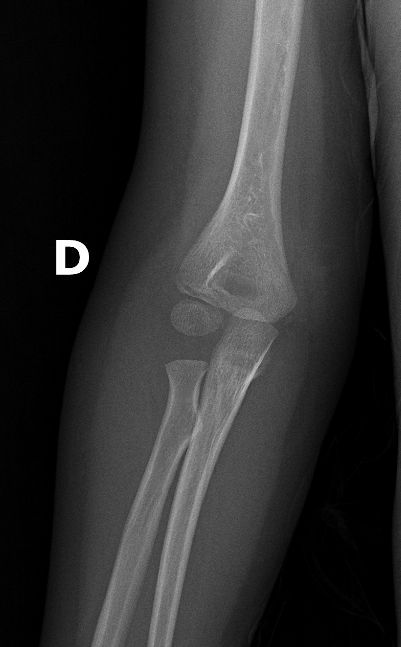

Describe the abnormality demonstrated.

Oblique fracture of the mid-shaft ulna and dislocation of the radio-capitellar joint (Monteggia)